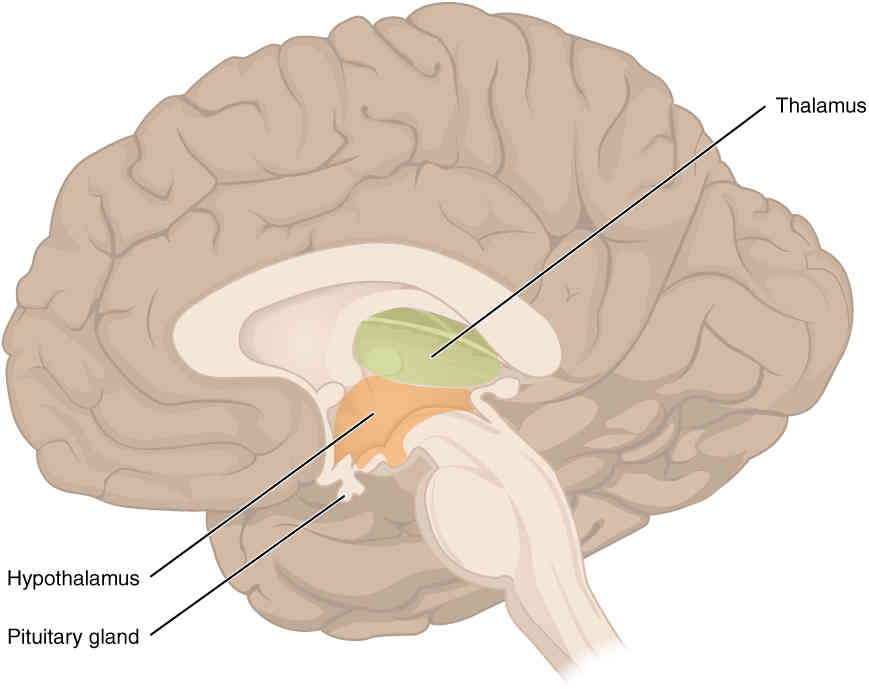

This page is under construction. For now, it is just a resource of the images found in the OpenStax Anatomy and Physiology Handbook. It wil slowly change into a revision tool. Each slide has a number. Use this to refer to the slide. When completed, it will have an unlabelled section, with labelled slides in parallel. On the unlabelled slides, write your answer and use the labelled slide to assess yourself. Keep track by also noting the number on each slide. Improvement at each attempt is important, more so than full marks on a first attempt.